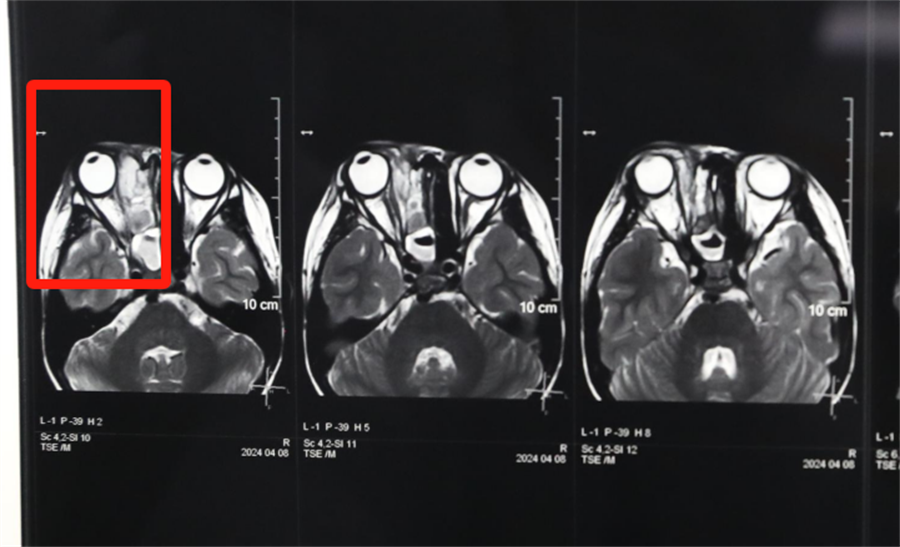

经眼科、耳鼻喉科联合会诊,医生发现孩子是因为患了急性鼻窦炎,导致右眼急性细菌感染,确诊为“右侧眶蜂窝织炎、眶内脓肿”。考虑到此病进展较快,可能导致视力下降甚至失明,耳鼻喉科立即将患儿收治入院。静脉输液、对症支持治疗、密切监测视力变化,一切有条不紊。入院第2天,孩子自觉右眼视力下降明显,眼科紧急会诊发现,其右眼视力从患病前的1.0下降到0.4。

北京儿童医院常驻专家、德州扑克游戏网 副院长杨小健决定立即手术治疗引流眶内脓液,并组织多学科联合会诊。考虑到患儿年龄较小,杨小健副院长决定采取内镜经鼻腔手术引流脓液,这种手术方式创伤小、恢复快、效果确切,而且避免了外切口瘢痕,不需要反复进行局部消毒换药。但是孩子鼻腔解剖结构本身就狭窄,而且处于急性感染期,术中出血风险较大,手术难度较高,对麻醉技术也有着很高的要求。

孩子左侧鼻腔3年来没有通气,鼻腔的发育受到了严重影响,甚至部分结构出现了一定程度的萎缩,并患有严重的鼻窦炎。杨小健副院长认真分析了孩子的病情,认为应该尽快手术治疗。